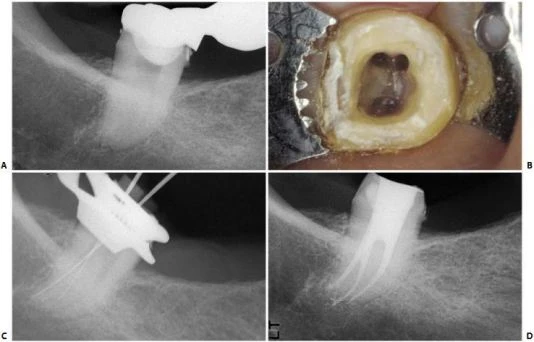

RCL 3 dưới đôi khi phải điều trị nội nha vì những lý do như đối với RCL 3 trên. Nó đặc biệt quan trọng khi đóng vai trò là răng trụ cuối cùng ở phía xa. Răng này có thể có hình dạng thân răng hoàn toàn bình thường nhưng hình thái chân răng lại khác hoàn toàn và dị dạng (hình 11.141, 11.142) Dù sao đi nữa, răng này cũng có thể được điều trị nội nha thành công (hình 11.143, 11.144). Ta mở xoang tủy tương tự như những răng khác.

Vì chân răng nghiêng xa, việc điều trị nó thường dễ hơn so với những gì ta nghĩ khi quan sát trên X-quang.

Hình  11.142.  RCL 3 dưới với 2 ống tủy xa và 1 ống gần.  A.  Phim trước điều trị. B.  Xoang mở tủy. C. Trong khi điều trị. D. Phim sau điều trị.